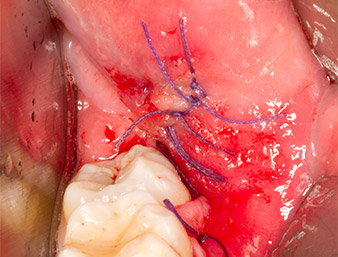

Puis le tissu osseux autogène (Fig. 13) est placé dans l’alvéole et le défaut osseux voisin (Fig. 14). Une membrane de collagène recouvre les fragments osseux à hauteur de l’os afin de protéger le nerf exposé (Fig. 15). Pour refermer le tissu mou ouvert, on utilise du fil de suture Vicryl, USP 4.0 (Fig. 16). Une préparation à base d’ibuprofène (Seractil 400 mg, 3x1) et un antibiotique associant amoxicilline et acide clavulanique (Augmentin 1 g, 2x1) sont prescrits en postopératoire.

Partie apicale de l'alvéole

Fig. 14 : La partie apicale de l’alvéole est recouverte du tissu autogène

Membrane de collagène

Fig. 15 : Le défaut est comblé par une membrane de collagène à hauteur de l’os afin de protéger le nerf. Les saignements marquent le début de la cicatrisation.

Sutures (fil Vicryl 4.0)

Fig. 16 : La plaie est suturée (fil Vicryl 4.0).